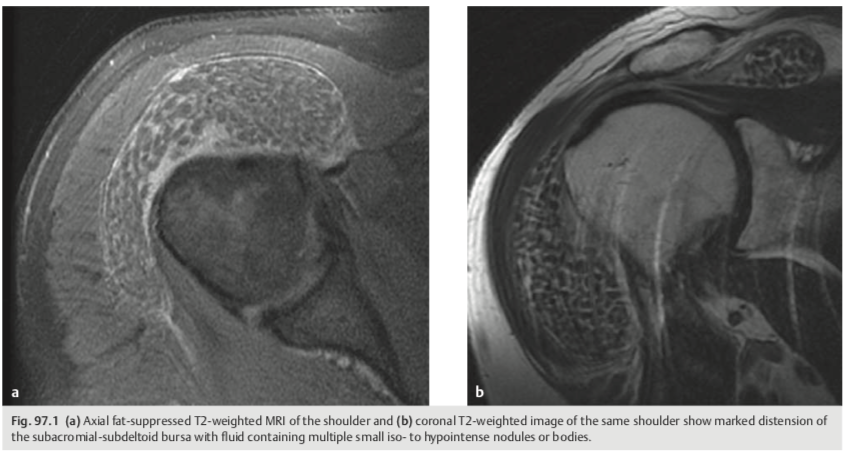

A 71-year-old man with shoulder pain and swelling